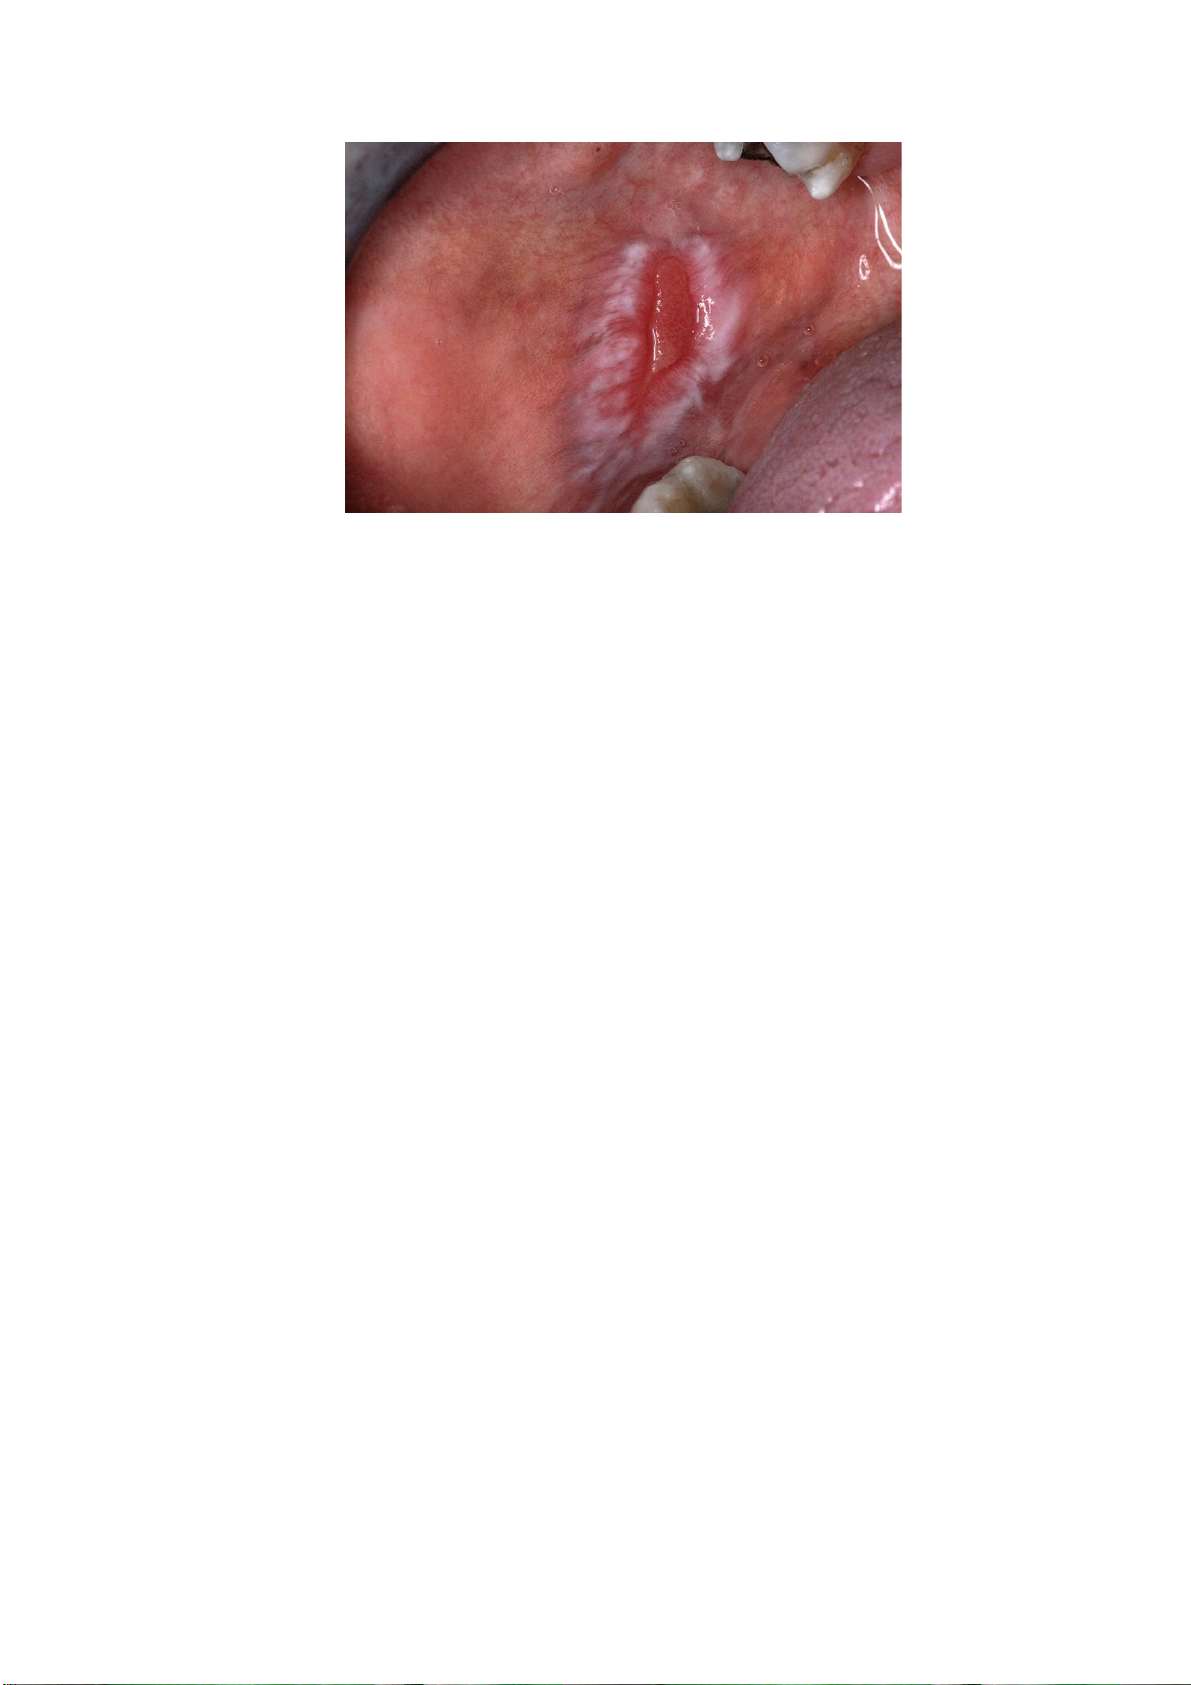

mụn cóc có thể phát triển thành SCC hoặc carcinôm mụn cóc. (a) (b)

Hình 2. (a) Bạch sản tăng sinh dạng mụn cóc ở nướu răng; (b) Biểu mô gai lát tầng tăng sừng

hóa (4x) với các nhú trên bề mặt và thấm nhập tế bào viêm ở mô đệm. Nguồn: Kumari và cộng sự, 2022 Hồng sản